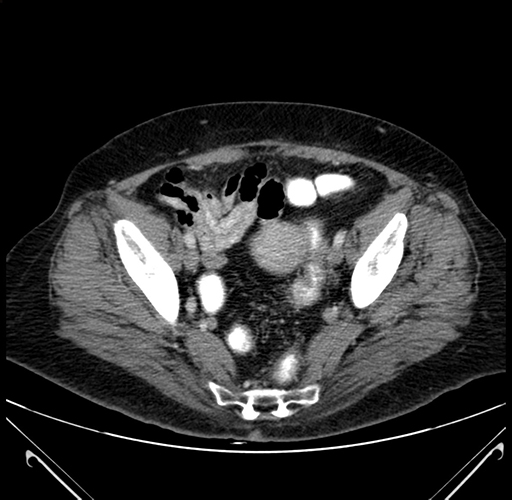

Axial Venous